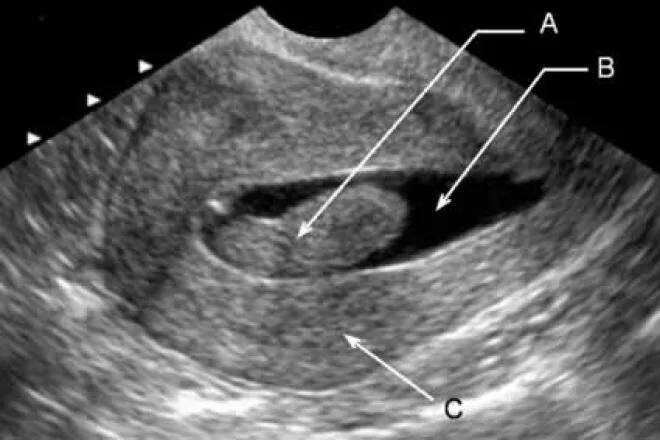

Согласно российским клиническим рекомендациям метод первой линии диагностики полипов матки — УЗИ органов малого таза, предпочтительно трансвагинальным доступом.

Наиболее информативно исследование, выполненное в первую фазу менструального цикла — с 5-го по 14-й дни.

При выявлении полипа матки по УЗИ малого таза следующим этапом гистероскопию считают золотым стандартом диагностики полипов эндометрия. С помощью этого исследования можно одномоментно удалить полип и выполнить гистологическое исследование.